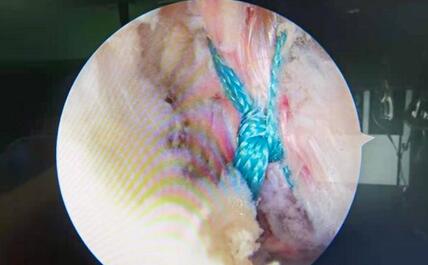

骨折复位固定后镜下观

手术开始,术中3D-C臂扫描采集数据,三维重建骨折位置及形态,天玑骨科机器人规划骨隧道位置,自动完成进针导向器定位。主刀医生张主任沿导向器打入导针,关节镜下再次验证导针位置满意,建立骨隧道,非可吸收线“R”形捆扎后交叉韧带止点部,复位骨折端。后交叉韧带位置,走形,张力均满意。

张主任介绍,自2019年我院引进天玑骨科机器人以来,在关节、脊柱、手外等骨科领域多个学科的临床手术中发挥了巨大的优势。本次天玑骨科机器人辅助后交叉韧带胫骨止点撕脱骨折复位内固定术,减少了术中重复操作步骤,手术时间更短,术中患者出血少,创伤小,恢复快。尤其是其定位精准,可安全避开腘窝处的血管神经,损伤较小。骨隧道精准定位,三维成像更加直观,骨折复位患者更加满意。